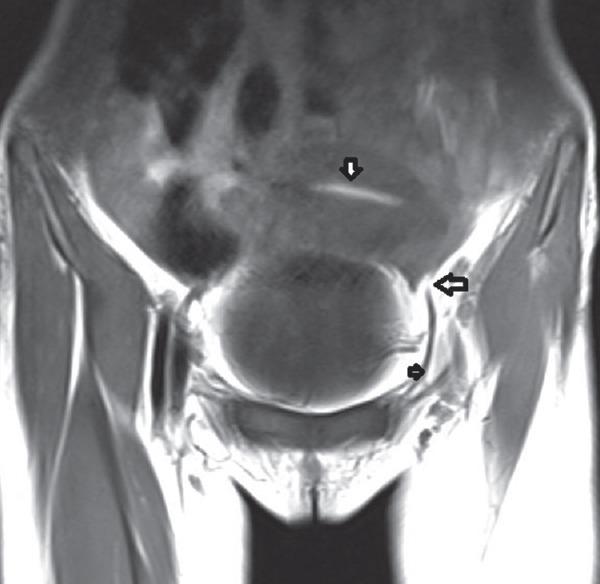

Among eight girls, two were infants and six were in the adolescent group. Clinical presentations included varied degree of genitourinary obstruction (7) and incidental finding (1). Genetic analysis of imperforate hymen suggested sporadic event (5), associations (2), and syndromic (1). Ultrasound and magnetic resonance imaging revealed the level of obstruction. Hymenectomy was done in neonate (1), adolescent (6), and one has been under observation. Abdominoperineal pull-through was done in concomitant proximal vaginal atresia.

8名女孩中,2名是婴儿,6名在青少年组。临床表现包括不同程度的泌尿生殖系统梗阻(7例)和偶然发现(1例)。处女膜闭锁的基因分析提示为散发事件(5例)、关联情况(2例)和综合征型(1例)。超声和磁共振成像显示了梗阻水平。1例新生儿、6例青少年接受了处女膜切除术,1例一直在观察中。对于合并近端阴道闭锁的情况进行了腹会阴拖出术。